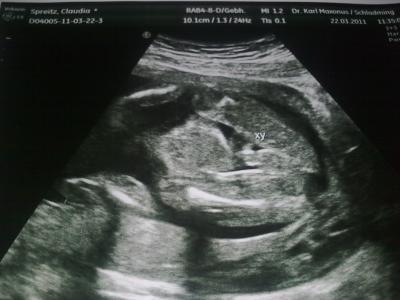

Hallo ihr Lieben!!! War heute (18+6) beim FA und meinem Baby gehts super gut und alles ist perfekt und auch zeitgerecht entwickelt! Beim Organscreening auch alles Bestens! Und beim Blick zwischen die Beinchen konnten wir gaaanz deutlich sehen: Wir bekommen einen süßen, kleinen Sohnemann!!!! Gaaaanz liebe Grüße, Claudia

Bild zu Juhuuuuu OUTING + Bildchen!!! =) - Forum für August - Mamis